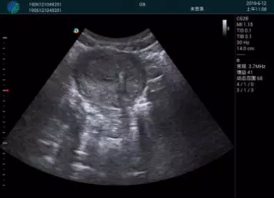

M20查看:囊內(nèi)回聲均勻,邊界清晰,囊壁光滑

M20引導(dǎo)抽吸術(shù)后囊腫消失,原區(qū)域空腔形成,脂肪層與腺體層架構(gòu)發(fā)生改變